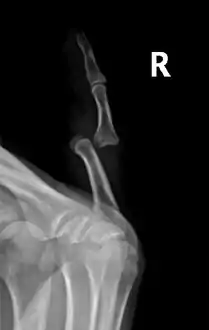

Radiograph of right fifth phalanx bone dislocation

Radiograph of right fifth phalanx dislocation resulting from bicycle accident

Right fifth phalanx dislocation resulting from bicycle accident